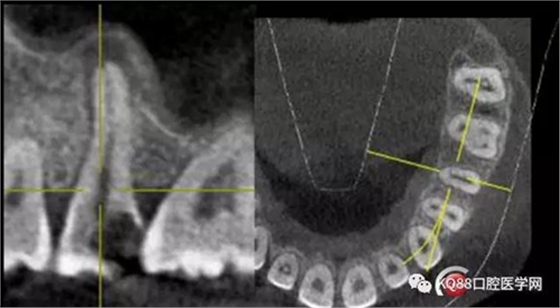

這兩張角度的截圖告訴我們這個牙齒一個典型的Y型根管,髓腔非常巨大,從根管口看,貌似一個根管口,但是根管銼下去以后,會兩個方向角度的分開。因?yàn)槲覀儸F(xiàn)在都是常規(guī)的機(jī)擴(kuò)與熱牙膠充填,建立直線根管口的暴露就變得非常重要,必須直線視野下操作,機(jī)擴(kuò)才不會發(fā)生扭曲折斷。目前市面上的根管銼有很多,M3,S3等,而此次我使用的是歐羅德卡PLEX軟銼,因?yàn)槭强谇?8贈送我的,所以我就先嘗試的使用了一下,我不會單方面的去評價(jià)比別的好,我覺得預(yù)備方法對了,都會很不錯,只能說一句這個用起來軟銼對后牙的預(yù)備確實(shí)不錯。根管預(yù)備,常規(guī)我都會先C銼疏通,如果直接15號很有可能會在根尖方形成臺階,以后就很難再下去了,當(dāng)C銼到達(dá)根尖孔后,予以初步測量長度,在用疏通機(jī)擴(kuò)針通入,然后一步步規(guī)范化開始,逐級預(yù)備,一個簡單的經(jīng)驗(yàn),如果當(dāng)使用的銼不容易到達(dá)根尖時,不要著急,用上一號,繼續(xù),再回來,就可以了,不然形成臺階,就很難操作了,常有人會覺得擴(kuò)根時,突然發(fā)現(xiàn),下不去了,排除斷針的可能性的話,臺階是最重要的,擴(kuò)根時,1%次氯酸鈉變沖洗,變預(yù)備,防止碎屑推出根尖孔,我沖洗常使用1%次氯酸鈉與蒸餾水,再充填前,會使用EDTA沖洗液去除根管壁油污。